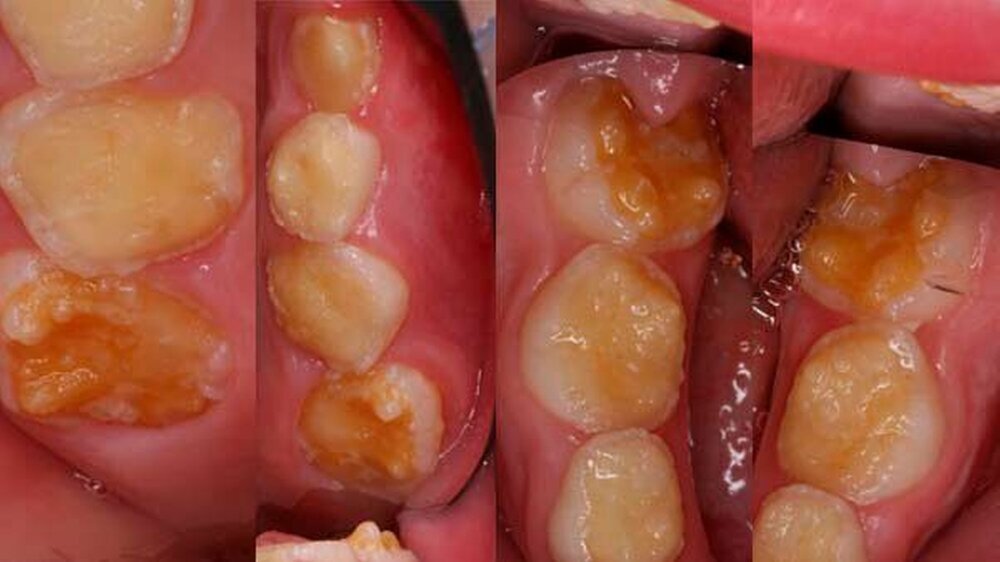

Der klinische Befund zeigte an beiden Dentitionen eine rauhe, zum Teil verminderte, bis fehlende Schmelzdicke und eine teilweise bräunliche Zahnverfärbung. Letztere wurden auch durch exogene Pigmenteinlagerung verursacht (Abbildung 1b und Abbildung 2).